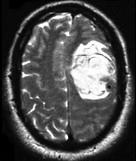

- 单项选择题男,52岁, 既往检查有脑动静脉畸形,突发站立不稳伴恶心呕吐4小时, 请结合影像图像选择最可能的诊断 ( )

A、脑出血

B、脑脓肿

C、脑转移瘤

D、脑梗死

E、颅内动脉瘤